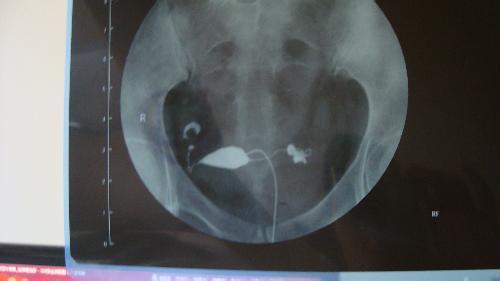

相信了解输卵管检查的女性朋友都知道, 输卵管造影 是用来检查女性输卵管通畅与否...[详情]

相信很多女性在没有接触过输卵管检查方面的相关知识前,对 输卵管造影术 是很一头...[详情]

9月15日一早,相关术前检查有条不紊地进行着:签订术前告知书、抽血、测体温抽血时...[详情]